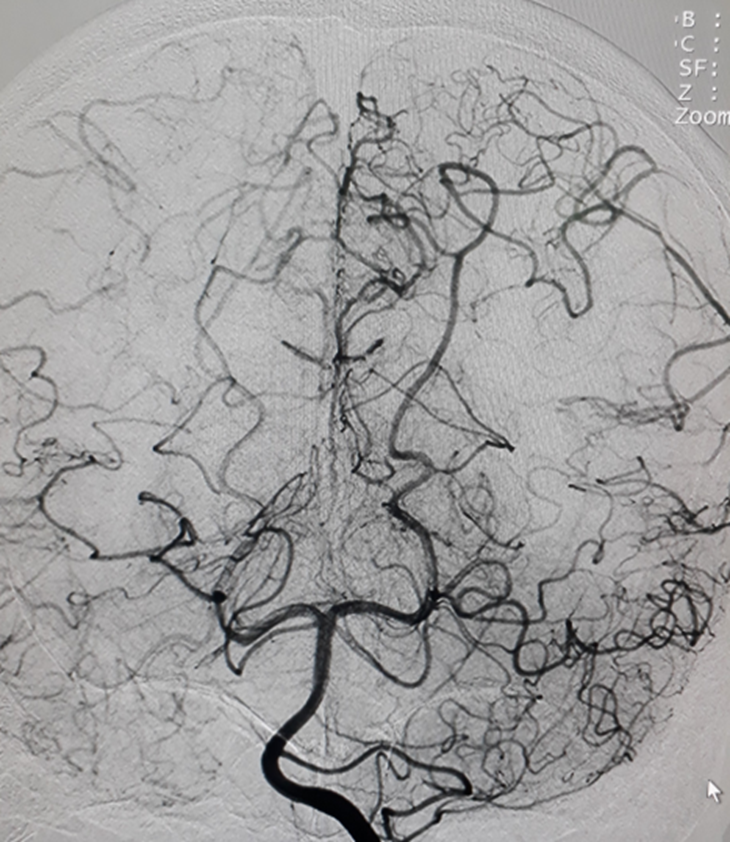

Hình chụp DSA động mạch cảnh trong phải và trái: hẹp khít động mạch não giữa hai bên đoạn M1.

Hình chụp DSA động mạch cảnh trong trái: hẹp khít động mạch cảnh trong trái đoạn mấu giường.

Hình chụp DSA động mạch đốt sống: bàng hệ cho hệ tuần hoàn trước từ hệ thống tuần hoàn sau

Bệnh Moya Moya là bệnh lý mạch máu hẹp tại gốc một số động mạch lớn trong sọ thuộc tuần hoàn trước (thuộc động mạch cảnh trong). Quá trình hẹp dần dần nên cơ thể thích nghi bằng các tuần hoàn bàng hệ bù cho vùng thiếu hụt tuần hoàn. Tuần hoàn bàng hệ phát triển tại chỗ hẹp bằng rất nhiều mạch máu nhỏ và yếu, dễ hình thành các phình mạch nhỏ và vỡ gây chảy máu não. Nếu tuần hoàn bàng hệ một lúc nào đó không đủ cấp máu cho não sẽ gây nên nhồi máu não tái đi tái lại. Trên chụp mạch, các mạch nhỏ tại chỗ hẹp tạo nên hình “những làn khói tỏa” (puff of smoke). Bệnh lấy tên một bác sĩ người Nhật là người đầu tiên mô tả về bệnh này trong y văn.